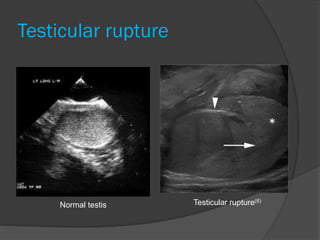

Testicular rupture

Normal testis Testicular rupture(6)

Testicular rupture Normal testisTesticular rupture(6)